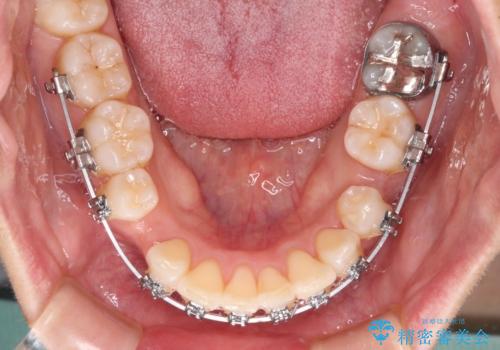

前歯のデコボコを抜歯矯正で改善 メタル装置で費用を抑える

- 矯正装置

- メタルブラケット

非抜歯矯正ではデコボコを解消することでより口元が突出してしまうため、上下左右の小臼歯4本の抜歯を行い、ワイヤー装置による矯正治療を行うこととしました。

もう少し口元の突出感を改善したかったのですが、舌の突出癖が影響し下顎前歯が唇側に押させる仕上がりとなりました。